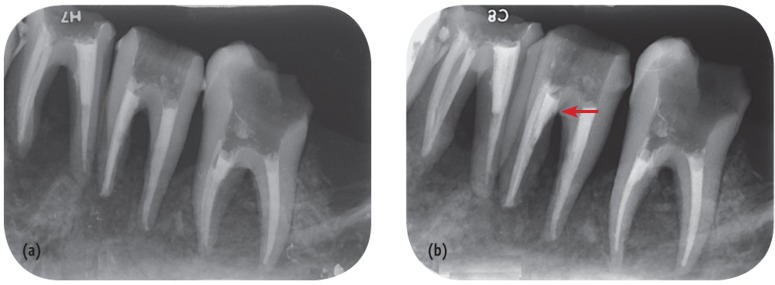

Intraoral conventional and digital radiography were done using E Speed dental films (Kodak, Rochester, NY, USA) and Digora Optime (Soredex, Tuusula, Finland) size 2 PSP receptor (85 - 167 microns pixel size and 6 - 8 LP/mm resolution) with Minray intraoral x-ray unit (Soredex). To hold the image receptors in a fixed and repeatable position, a film holder was made with putty paste (Asia Chemi Teb Mfg Co., Tehran, Iran). The mandible was placed on a table and mounted on a wooden block to facilitate the movement of the x-ray tube. Two images were taken from each tooth in two different directions including perpendicularly and 10° distal tube shift relative to the long axis of the teeth. Exposure times were 0.2 and 0.12 seconds for conventional and PSP radiography, respectively, with the exposure settings of 7 mA and 60 kVp. Conventional radiographs were processed in an automatic processor (Hope DentalMax X-ray processor, ClassicXray. com, Rolla, MO, USA) and then mounted (Figure 2). Digital receptors were kept inside a black plastic bag to minimize the effect of environmental light and were then scanned using a Digora scanner (Soredex). The images were stored in JPEG format (Figure 3).

In our study, the diagnostic value of periapical radiographs in diagnosing strip and root perforations was high mainly because these perforations were made on mesial or distal sides of the roots and radiopaque materials were placed in canals. Although the diameter of perforations were small and similar to the diameter of endodontic instruments, the results obtained in the current study showed that the diameter of perforation did not influence the accuracy of periapical radiographs which is similar to a previous study.7 Changing the horizontal angulation of the radiation source increases the diagnostic ability of PRs especially for diagnosis of strip perforations where the location of perforation could be masked by the concavity of the root (Figures 2 and 3).7,34 Consequently, it was possible to highly diagnose strip and root perforations.